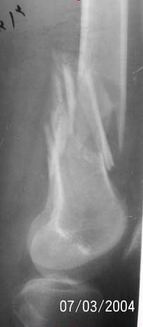

A 34 year old male was injured in a car accident.

The femur injury was treated by long retrograde interlocking nail.